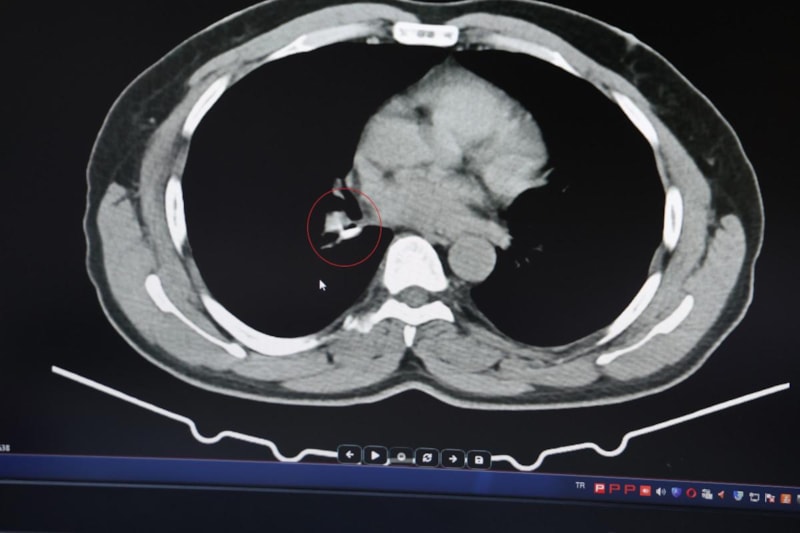

Yapılan tomografi ve bronskokopi işlemlerinde akciğere yerleşen maddenin yutulan silikon olduğu belirlendi. Silikonun çıkartılmasıyla hastanın tarifine göre şikayetlerinin ortadan kalktığı belirtildi.

Şenyiğit, o maddenin zamanla akciğer yapısının özelliğini aldığını ve orada yabancı bir madde olarak kaldığına değinerek, "Hastamıza maalesef 2 yıldan beri astım tanısı konulmuş ve sürekli tedavi verilmiştir. Hasta bize geldiği zaman yapılan tomografide sağ akciğer ana bronşun distalinde şüpheli lezyon gördük.

Uyguladığımız bronskokopide yabancı maddenin silikon olduğunu tespit ettik. Onu çıkardıktan sonra da hastada bir rahatlama meydana geldi" dedi.